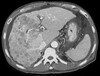

What pathology is seen here?

243

Hepatocellular Carcinoma (HPC)

What pathology is seen here? Label A-D

Hepatocellular Carcinoma (HPC) -Multiphase study A: Non contrast: Mass is hypodense B: Arterial phase: Aorta bright, tumour enhanced, non uniform enhancement (mish mash) C: Portal venous phase D: Delayed phase